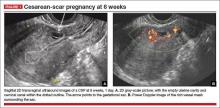

• empty uterine cavity and cervical canal (FIGURE 1A)

• close proximity of the gestational sac and the placenta to the anterior uterine surface within the scar or niche of the previous cesarean delivery (FIGURES 1B, 2A, and 2B)

• color flow signals between the posterior bladder wall and the gestation within the placenta (FIGURES 1B, 2B, and 3B)